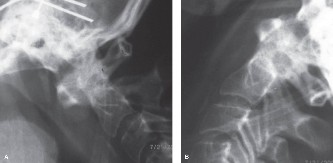

CASE 1 A 63-year-old male sustained a hyperextension injury to his neck while diving into a pool. Upon presentation, he reports decreased sensation in his hands and decreased strength in his arms and wrists, but no lower extremity complaints. On motor examination, he has 5/5 strength in his deltoids and elbow flexors and 4/5 strength in the elbow extensors, wrist extensors, and finger flexors. Lower extremity motor examination is normal. Sensation is decreased to light touch in both hands. Otherwise his sensation is preserved. Images of his cervical spine are shown in Figures 1–1 to 1–3.

Figure 1–1

Figure 1–2

Figure 1–3

The correct answer is (B). The clinical scenario describes a patient with central cord syndrome (CCS). CCS continues to be the most common incomplete spinal cord injury accounting for 15.7% to 25% of all spinal cord injuries. The characteristic presentation is an extension moment injury in a previously spondylotic and stenotic spine. Figures 1–1 to 1–3 demonstrate a spondylotic spine with central narrowing and CSF effacement that is worst at the C3–4 level. Bleeding, edema, and/or Wallerian degeneration lead to damage of the lateral corticospinal tract which is the main descending motor tract in the spinal cord. The more central anatomic position of the homunculus to the upper extremities places them at greater risk than those to the lower extremities. As such, injury to the lateral corticospinal tract is characterized by upper more than lower extremity involvement and motor deficits being more pronounced than sensory deficits.